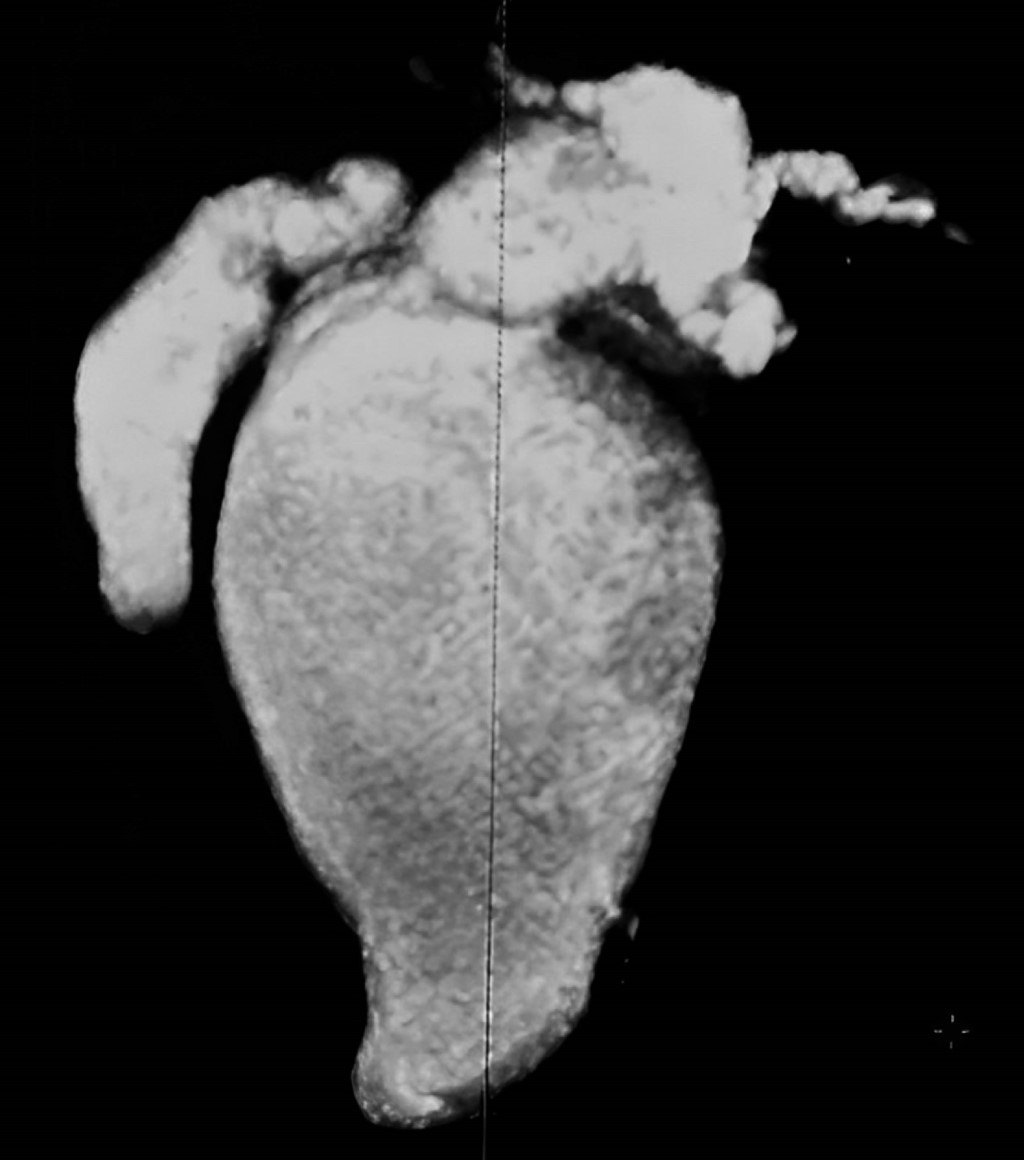

In her home, a hepatic and biliary tract ultrasound (HBVUS) was performed to interpret the presence of a hepatic cyst. Later, an M-RC was performed in Pachuca, Hidalgo, which confirmed the general surgeon's diagnosis of a common bile duct cyst. Due to a lack of resources, the surgeon referred her to the HCGFAA. Laboratory tests were performed (Table 1), and a new CR-M was performed (Figures 3 and 4), which showed a modified QC-IVA-Todani cyst (Figure 2).

Findings: an atrophic gallbladder without the presence of gallstones, a 7.6 mm cyst in the cystic duct, saccular dilatation of the intrahepatic and extrahepatic bile duct with a diameter of 18 mm in the right hepatic, 15 mm in the left hepatic duct and a confluence zone of 33 mm (carina) was seen. A maximum dilatation of the common bile duct of 70 mm, distal common bile duct of 23 mm, and the duct of Wirsung with normal dimensions were observed.